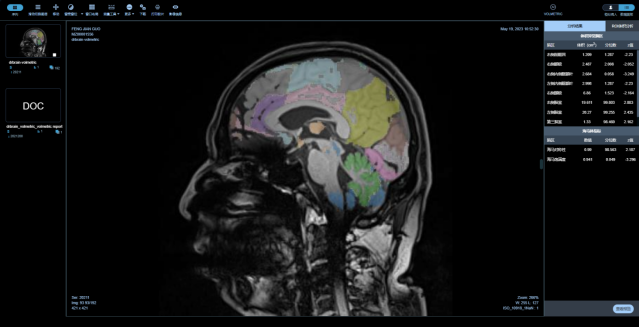

是專注在中樞神經(jīng)系統(tǒng)疾病的人工智能診斷分析平臺,基于醫(yī)未自行搭建的全年齡段中國人群全腦結(jié)構(gòu)影像數(shù)據(jù)庫,結(jié)合前沿的大數(shù)據(jù)分析和人工智能等核心技術(shù),快速、精準(zhǔn)評估全腦結(jié)構(gòu)變化、腦白質(zhì)病變、微出血灶及腦血流量等,以量化、直觀的結(jié)果,輔助臨床做出超早期的精準(zhǔn)診斷及疾病進(jìn)展預(yù)測。

最全面的分區(qū)

最全面的腦結(jié)構(gòu)分區(qū),快速獲取全腦100個精細(xì)腦區(qū)共165項(xiàng)指標(biāo),精度達(dá)到毫米級

量化、直觀的報告(部分)